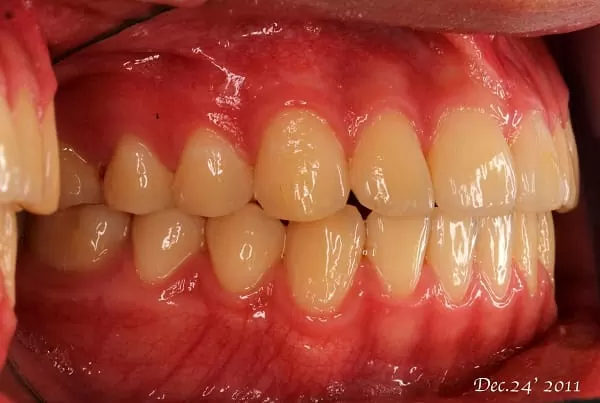

矯正後

綜合上述原因,成年人雖然過了生長發育期,當有牙齒齒列不正的問題,亦應諮詢矯正專科醫師,若沒有牙周病,牙周狀況良好,也可以透過矯正方式幫助牙齒調整至比較適當的位置,恢復比較良好的咬合狀況。所以成年人的矯正考量跟學齡兒童及青春期的少年是不一樣的。